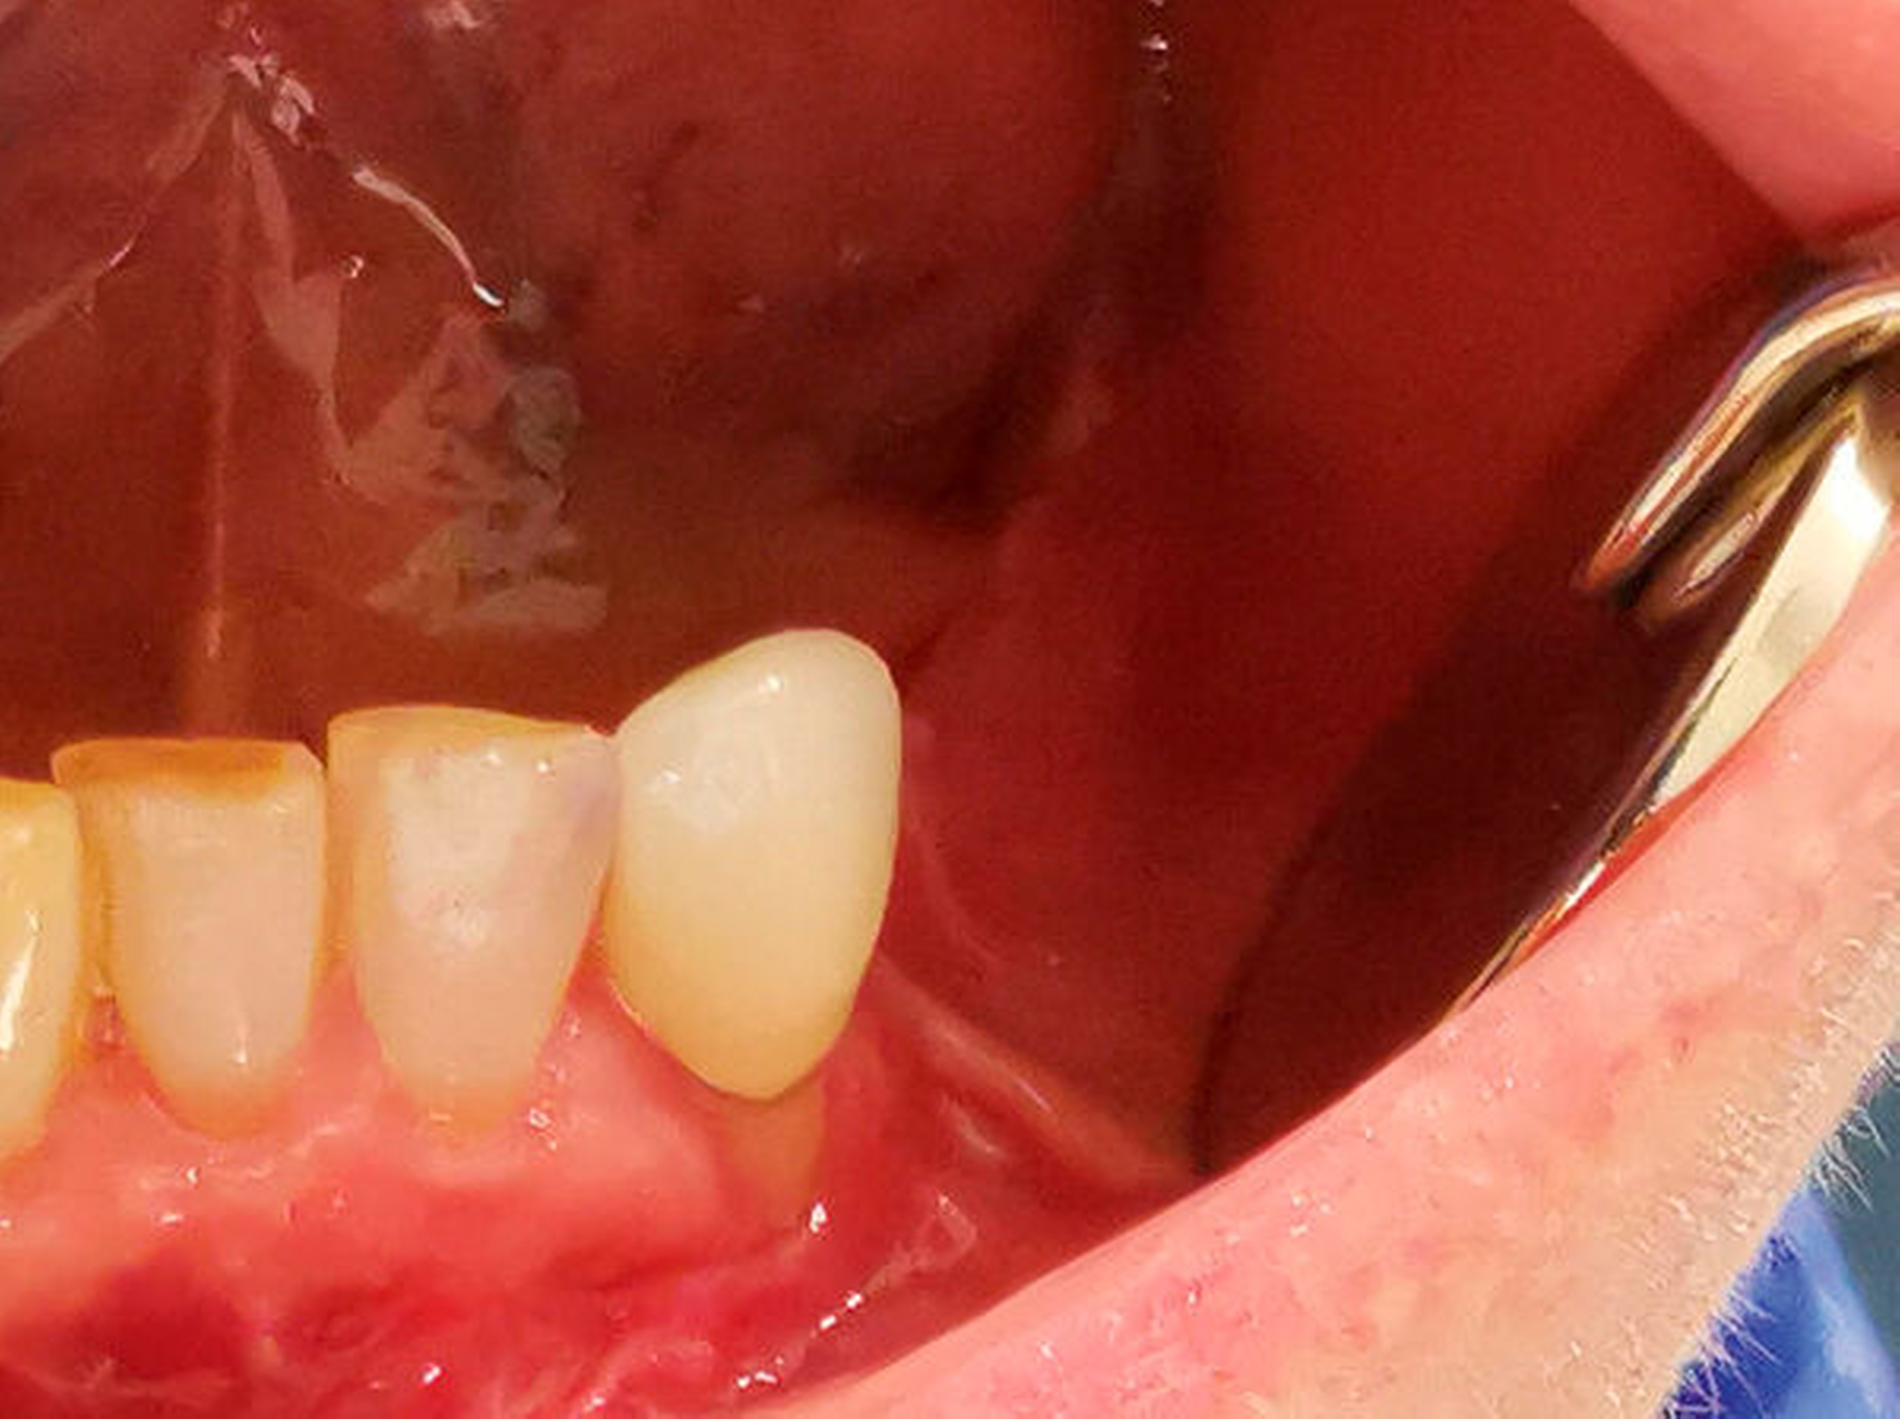

Aufgrund der seit einer Woche bestehenden Beschwerdesymptomatik mit Schmerzen im Bereich des linken Unterkiefers zeigte sich ein reduzierter Allgemein- und Ernährungszustand. Extraoral zeigte sich eine ausgeprägte, weiche Schwellung paramandibulär links. Der Unterkieferrand war zu jedem Zeitpunkt durchtastbar. Es zeigte sich eine Anästhesie im Versorgungsgebiet des Nervus mentalis links. Intraoral präsentierte sich eine Schwellung im Vestibulum sowie eine geringe Schwellung im Mundboden, ein Wurzelrest 34 sowie eine negative Sensitivität auf Kälte an den Zähnen 33 und 32. Im Oberkiefer zeigte sich ein prothetisch suffizient versorgtes Gebiss. Auch intraoral bestand eine Anästhesie im Versorgungsgebiet des Nervus mentalis links.

Der intraoperative Situs zeigte nach Abklappen des Mukoperiosts die Zugangskavität der alio loco durchgeführten Wurzelspitzenresektion. Der Wurzelrest 44 ist hierbei noch in situ (Abbildung 5).